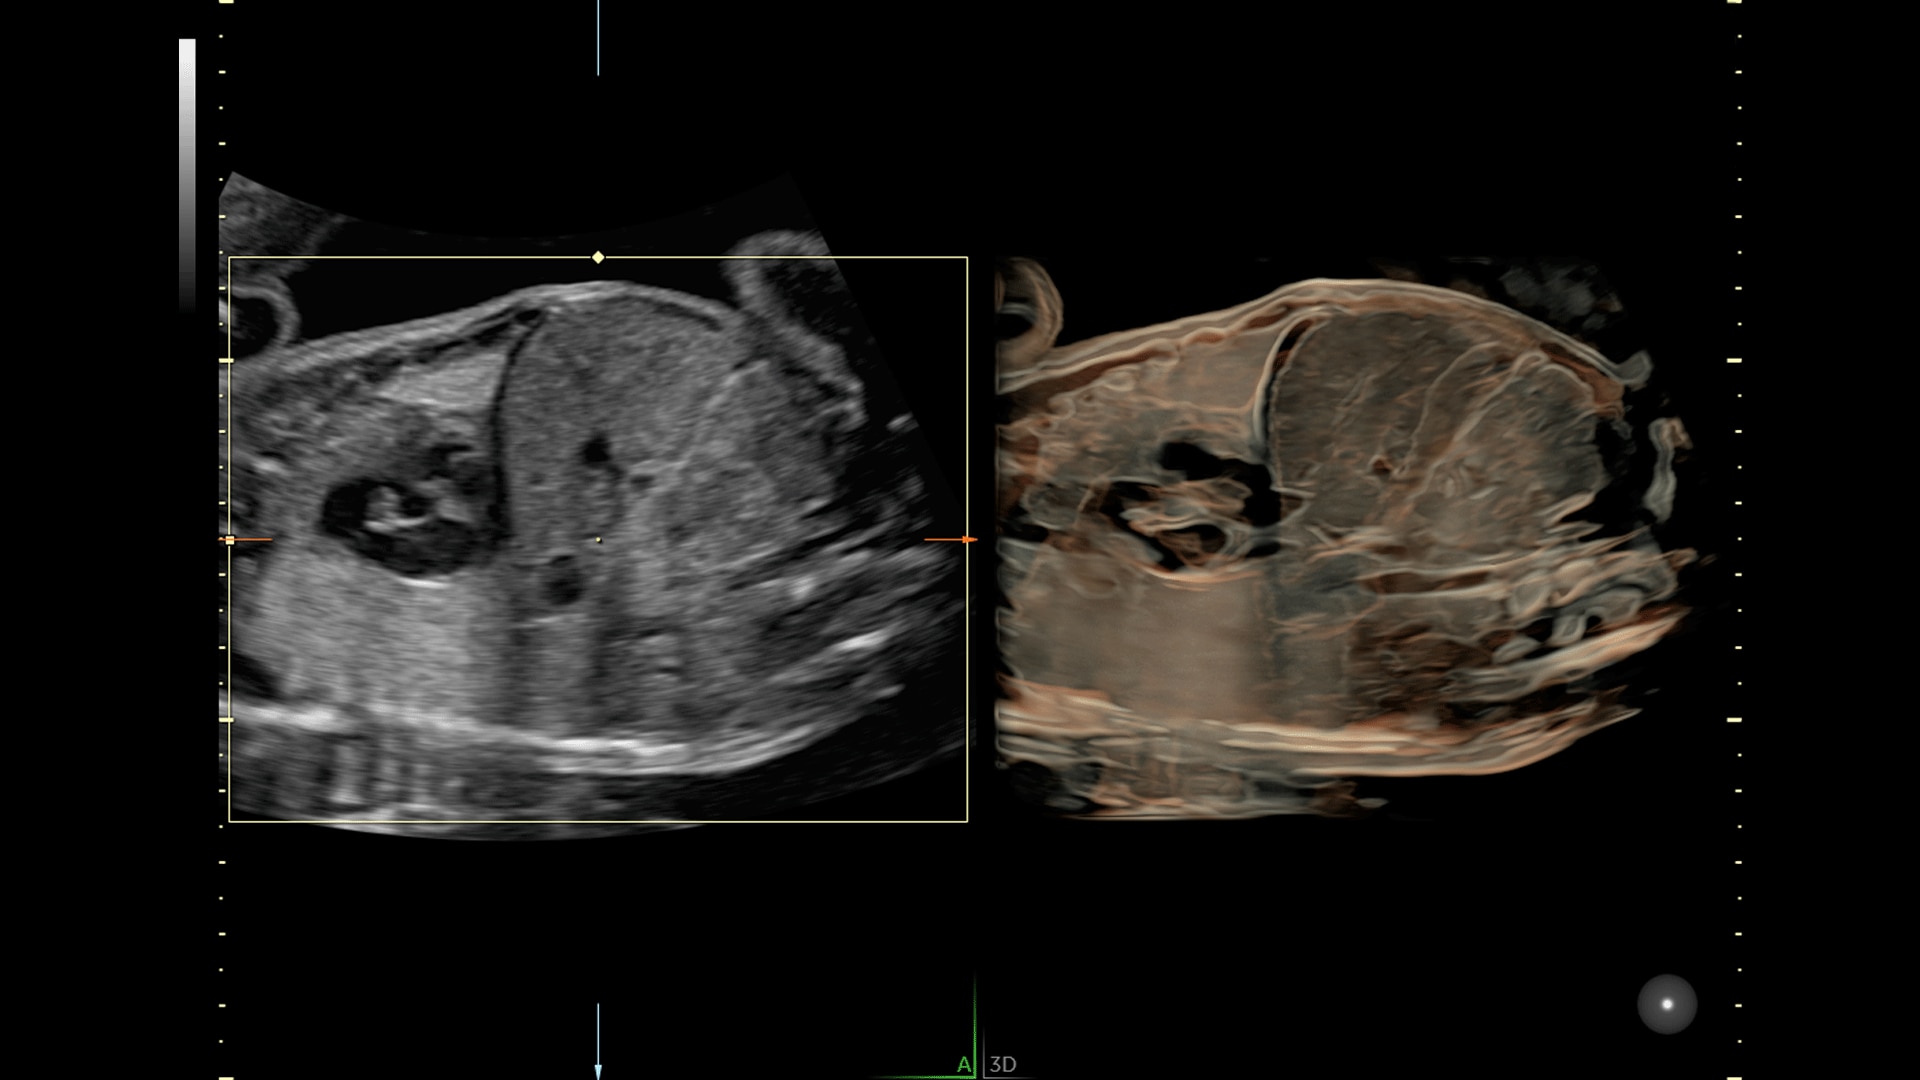

Amplify imaging performance and simplify scanning with our most advanced architecture

Extraordinary clarity and definition so you can focus on early detection and intervention.

Faster.Sharper. Clearer.

Faster.Sharper. Clearer.